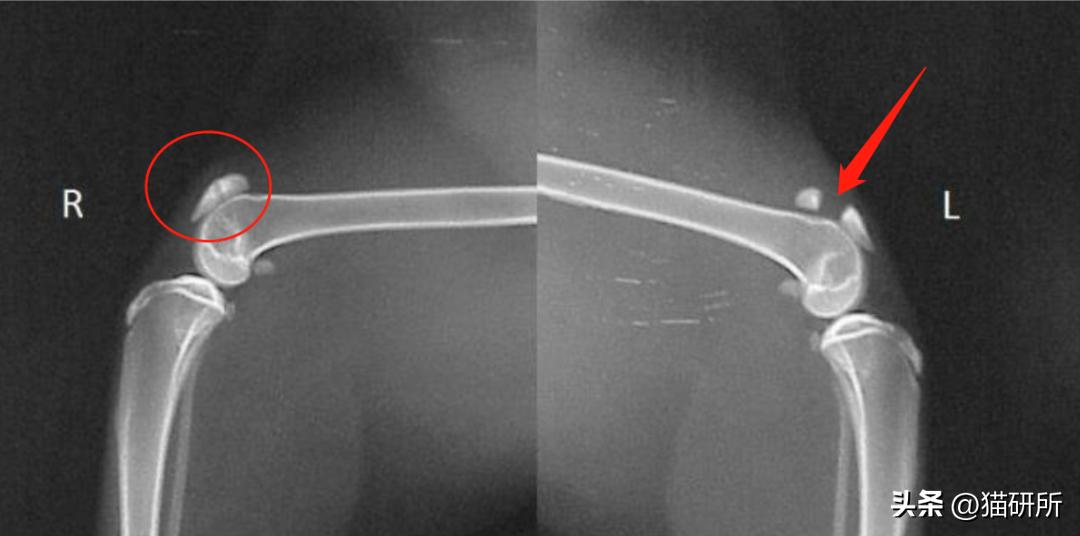

然而2周后复诊却发现病情恶化了。在没有任何创伤的情况下,Zora左后肢的髌骨竟然骨折了。

左后肢髌骨处骨折 图自:Knees & Teeth Case Series Presentation

Spaz的后肢X光检查

图自:引文[1]

· 出现跛行和髌骨问题的猫咪73%都是双侧髌骨骨折,且40.8%的猫咪除了髌骨骨折,髋臼、胫骨、坐骨、髂骨等地方也出现了1~6次骨折。

红圈为患病猫咪常出现骨折的部位

图自:引文[3]